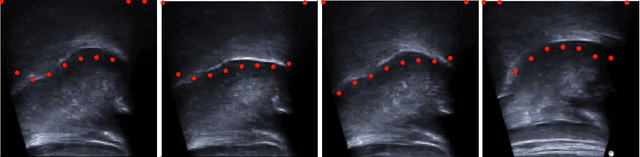

Abstract:One usage of medical ultrasound imaging is to visualize and characterize human tongue shape and motion during a real-time speech to study healthy or impaired speech production. Due to the low-contrast characteristic and noisy nature of ultrasound images, it might require expertise for non-expert users to recognize tongue gestures in applications such as visual training of a second language. Moreover, quantitative analysis of tongue motion needs the tongue dorsum contour to be extracted, tracked, and visualized. Manual tongue contour extraction is a cumbersome, subjective, and error-prone task. Furthermore, it is not a feasible solution for real-time applications. The growth of deep learning has been vigorously exploited in various computer vision tasks, including ultrasound tongue contour tracking. In the current methods, the process of tongue contour extraction comprises two steps of image segmentation and post-processing. This paper presents a new novel approach of automatic and real-time tongue contour tracking using deep neural networks. In the proposed method, instead of the two-step procedure, landmarks of the tongue surface are tracked. This novel idea enables researchers in this filed to benefits from available previously annotated databases to achieve high accuracy results. Our experiment disclosed the outstanding performances of the proposed technique in terms of generalization, performance, and accuracy.

Abstract:The progress of deep convolutional neural networks has been successfully exploited in various real-time computer vision tasks such as image classification and segmentation. Owing to the development of computational units, availability of digital datasets, and improved performance of deep learning models, fully automatic and accurate tracking of tongue contours in real-time ultrasound data became practical only in recent years. Recent studies have shown that the performance of deep learning techniques is significant in the tracking of ultrasound tongue contours in real-time applications such as pronunciation training using multimodal ultrasound-enhanced approaches. Due to the high correlation between ultrasound tongue datasets, it is feasible to have a general model that accomplishes automatic tongue tracking for almost all datasets. In this paper, we proposed a deep learning model comprises of a convolutional module mimicking the peripheral vision ability of the human eye to handle real-time, accurate, and fully automatic tongue contour tracking tasks, applicable for almost all primary ultrasound tongue datasets. Qualitative and quantitative assessment of IrisNet on different ultrasound tongue datasets and PASCAL VOC2012 revealed its outstanding generalization achievement in compare with similar techniques.

Abstract:Medical ultrasound technology is widely used in routine clinical applications such as disease diagnosis and treatment as well as other applications like real-time monitoring of human tongue shapes and motions as visual feedback in second language training. Due to the low-contrast characteristic and noisy nature of ultrasound images, it might require expertise for non-expert users to recognize tongue gestures. Manual tongue segmentation is a cumbersome, subjective, and error-prone task. Furthermore, it is not a feasible solution for real-time applications. In the last few years, deep learning methods have been used for delineating and tracking tongue dorsum. Deep convolutional neural networks (DCNNs), which have shown to be successful in medical image analysis tasks, are typically weak for the same task on different domains. In many cases, DCNNs trained on data acquired with one ultrasound device, do not perform well on data of varying ultrasound device or acquisition protocol. Domain adaptation is an alternative solution for this difficulty by transferring the weights from the model trained on a large annotated legacy dataset to a new model for adapting on another different dataset using fine-tuning. In this study, after conducting extensive experiments, we addressed the problem of domain adaptation on small ultrasound datasets for tongue contour extraction. We trained a U-net network comprises of an encoder-decoder path from scratch, and then with several surrogate scenarios, some parts of the trained network were fine-tuned on another dataset as the domain-adapted networks. We repeat scenarios from target to source domains to find a balance point for knowledge transfer from source to target and vice versa. The performance of new fine-tuned networks was evaluated on the same task with images from different domains.

Abstract:Ultrasound imaging is safe, relatively affordable, and capable of real-time performance. One application of this technology is to visualize and to characterize human tongue shape and motion during a real-time speech to study healthy or impaired speech production. Due to the noisy nature of ultrasound images with low-contrast characteristic, it might require expertise for non-expert users to recognize organ shape such as tongue surface (dorsum). To alleviate this difficulty for quantitative analysis of tongue shape and motion, tongue surface can be extracted, tracked, and visualized instead of the whole tongue region. Delineating the tongue surface from each frame is a cumbersome, subjective, and error-prone task. Furthermore, the rapidity and complexity of tongue gestures have made it a challenging task, and manual segmentation is not a feasible solution for real-time applications. Employing the power of state-of-the-art deep neural network models and training techniques, it is feasible to implement new fully-automatic, accurate, and robust segmentation methods with the capability of real-time performance, applicable for tracking of the tongue contours during the speech. This paper presents two novel deep neural network models named BowNet and wBowNet benefits from the ability of global prediction of decoding-encoding models, with integrated multi-scale contextual information, and capability of full-resolution (local) extraction of dilated convolutions. Experimental results using several ultrasound tongue image datasets revealed that the combination of both localization and globalization searching could improve prediction result significantly. Assessment of BowNet models using both qualitatively and quantitatively studies showed them outstanding achievements in terms of accuracy and robustness in comparison with similar techniques.